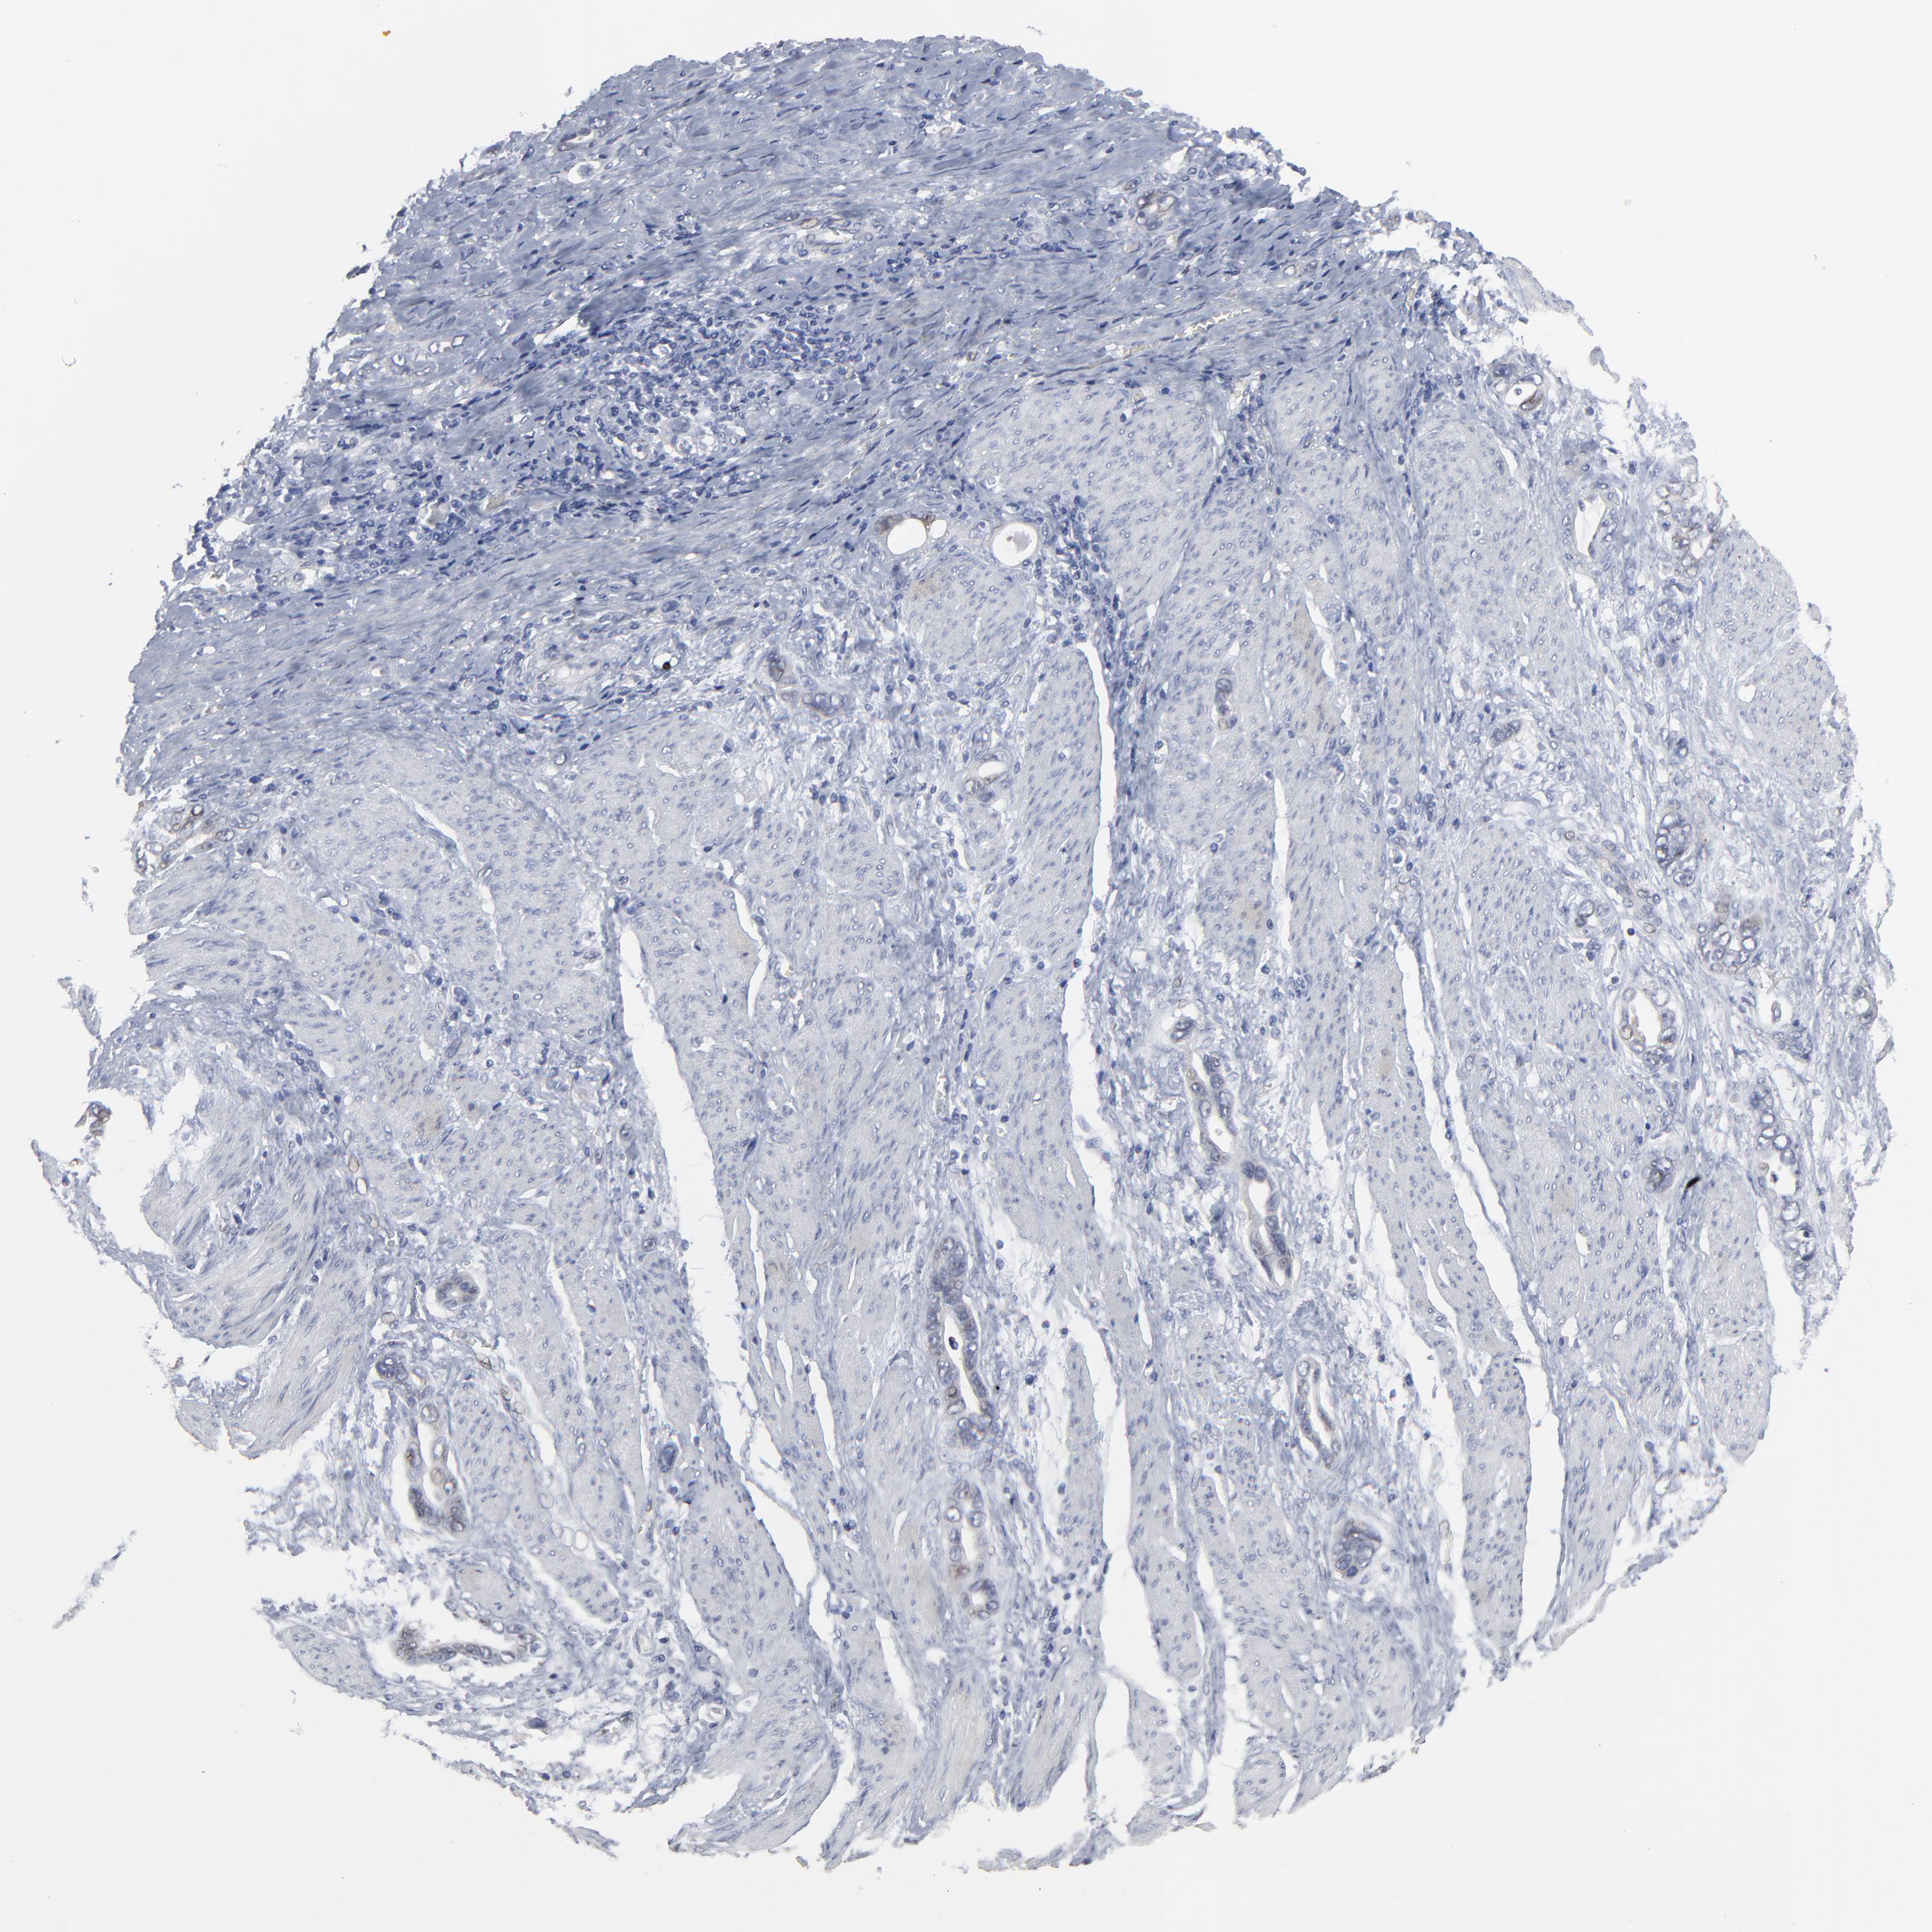

STOMACH CANCER - Protein expressioni

A mouse-over function shows sample information and annotation data. Click on an image to view it in a full screen mode. Samples can be filtered based on level of antibody staining by selecting one or several of the following categories: high, medium, low and not detected. The assay and annotation is described here.

Note that samples used for immunohistochemistry by the Human Protein Atlas do not correspond to samples in the TCGA dataset.

Antibody stainingi

Antibody staining in the annotated cell types in the current human tissue is reported as not detected, low, medium, or high, based on conventional immunohistochemistry profiling in selected tissues. This score is based on the combination of the staining intensity and fraction of stained cells.

Each image is clickable and will lead to virtual microscopy that enables deeper exploration of all samples and also displays staining intensity scores, fraction scores and subcellular localization as well as patient and tissue information for each sample.

Antibody HPA003435

Antibody HPA050204

Staining

High

Medium

Low

Not detected

Intensity

Strong

Moderate

Weak

Negative

Quantity

>75%

75%-25%

<25%

None

Location

Nuclear

Cytoplasmic/membranous

Cytoplasmic/membranous,nuclear

Adenocarcinoma, NOS